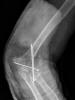

Fractura intertrocantérea de fémur, osteosíntesis